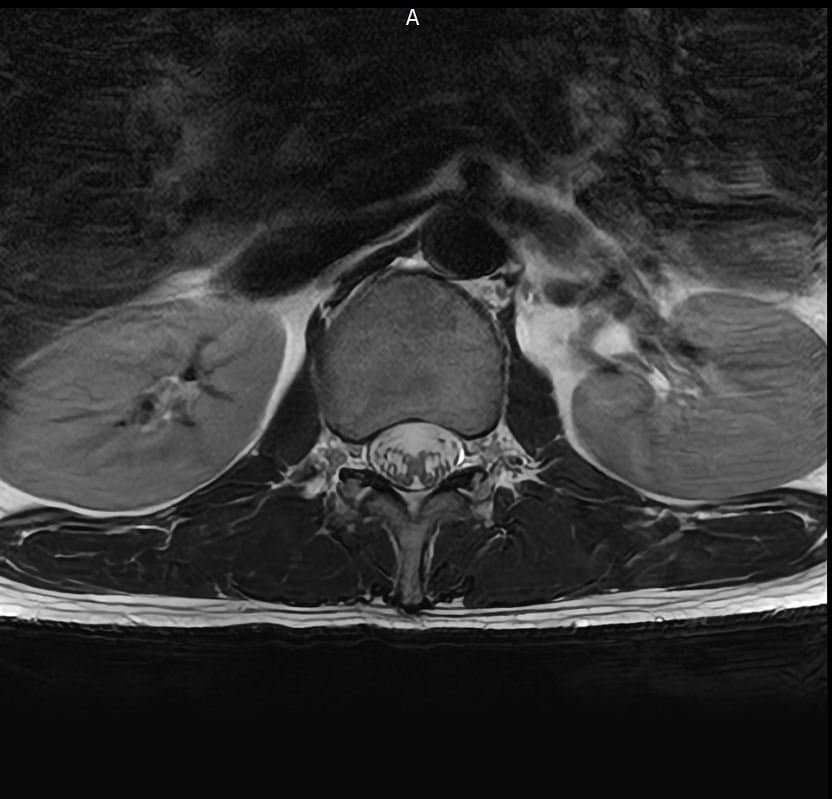

양쪽 엉덩이 염좌 6주째인데 mri 촬영한것좀 봐주세요

엉덩이 양쪽 염좌가 6주됨

방사통 없음 저림 없음 재채기 , 계단타기 전부 정상 , 숙일때 통증 없음

엉덩이 위쪽 바깥쪽 부분이 아픔 압통점 있음

177 / 66kg 약간의 퇴행성이 보인다는데 엉덩이 염좌와는 연관 없을꺼라고 하는데

영상과 증상을 종합해보면 전체적으로 척추배열은 양호하나, 요추4~5번과 요추5번~천추1번 사이의 디스크 수핵이 약간 검게 변한 퇴행성 변화가 관찰됩니다. 다만 신경을 심하게 압박하는 추간판탈출증 소견은 뚜렷하지 않습니다.현재 방사통이나 저림이 없고 특정부위에만 압통이 있다면 의료진의 소견대로 허리디스크보다는 근육 몇 인대문제일 가능성이 높습니다.말씀하신 부위는 염좌로 인해 예민해진 근막이나 인대가 완전히회복되지 않아 컨디션에 따라 통증이 반복될수 있습니다. 6주째 통증이 반복된다면 단순 휴식보다는 물리치료나 도수치료를 통해 굳어있는 근막을 풀어주는 것이 회복에 도움이 됩니다. 빠른쾌유를 빕니다!

MRI 영상상 관절 주변 조직의 부종이나 구체적인 염증 부위를 세밀하게 확인하는 과정이 꼭 필요해 보입니다.